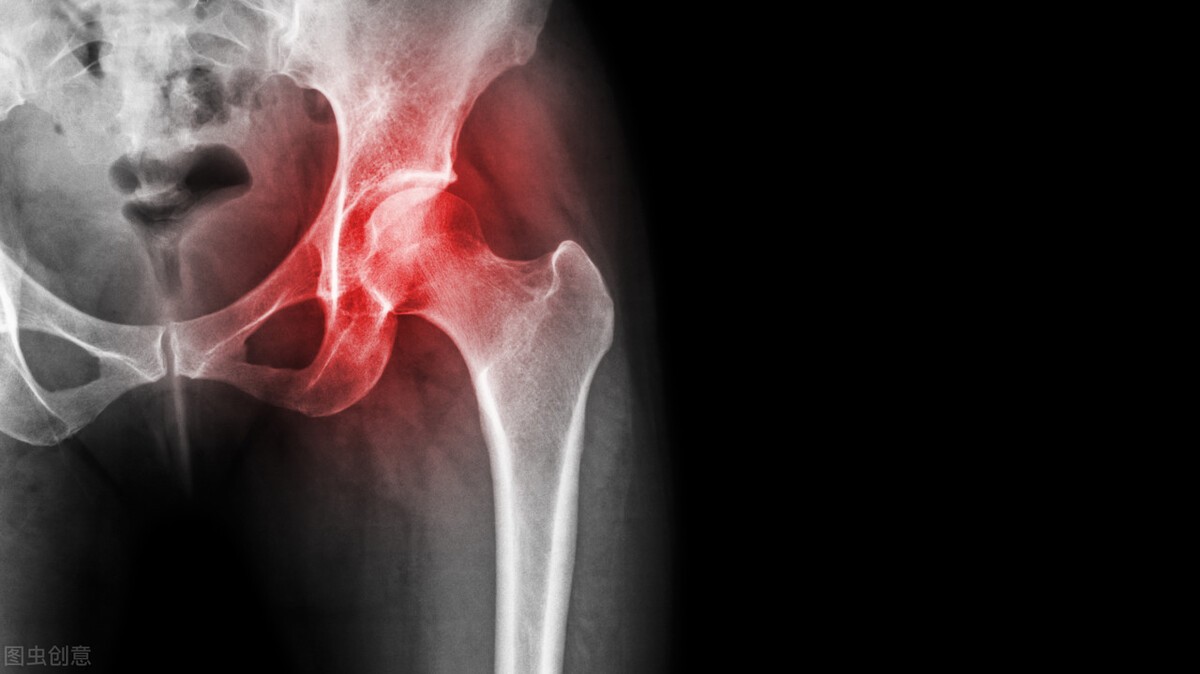

很多股骨头坏死的患者都会咨询这样的问题,那么人工髋关节国产的和进口的区别到底有多大?